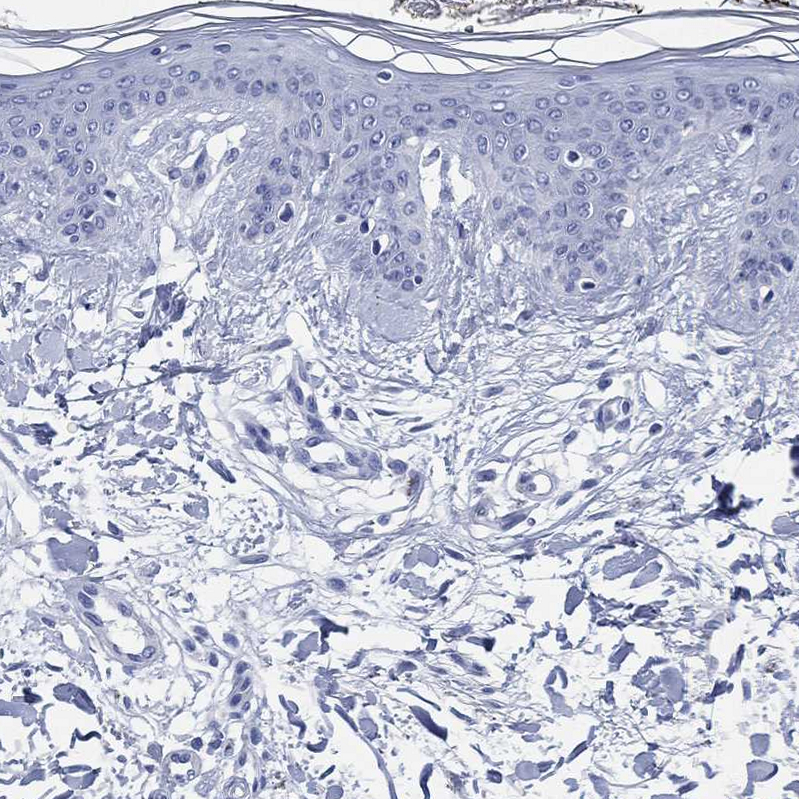

Immunohistochemical staining of human hypothalamus shows strong cytoplasmic positivity in neurons.